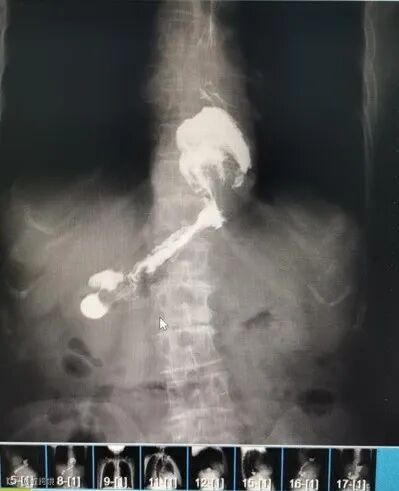

(患者影像照片)

食管裂孔疝指的是腹腔内的脏器(多数是胃)通过食管裂孔进入胸腔所导致的疾病。正常情况下,食管裂孔刚好可容纳食管通过。但如果腹腔内压力增大或食管裂孔周围结构过于松弛,腹腔内的脏器就可以通过食管裂孔进入胸腔,由此在医学上形成了食管裂孔疝。